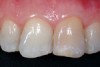

When a machined, smooth, and conical-shaped preparation is cut with conical carbide, the visual contrast between dentin and pulp tissue remnants (PTRs) is visually apparent and tactilely accessible (Figure 12). Microsurgeon dentists operating at 8x to 24x magnification with an operating microscope can leverage the optimized dentinal maps for direct visual recognition of tiny PTR s, even when the smallest hand file does not bind. Endodontists and dentists who elect to perform endodontics without microscopes benefit from the tactile advantage of the conical shape. In either case, the patient can benefit, because minimized gouging allows peri-cervical dentin (PCD) to be maintained. PCD is defined as the crucial dentin in the "neck of the tooth," from 4 mm coronal to crestal bone to 4 mm apical to crestal bone.

The resultant cavosurface outline is quite long and fairly narrow for the calcified tooth, and creates better potential for accuracy (Figure 18 and Figure 19). A final view of the access in Figure 20 shows the orientation of the palatal–incisal notch and the dentinal map, which is encountered as early as possible. The radiographic sequence (Figure 21, Figure 22, Figure 23 and Figure 24) teaches a new concept in accessing calcified canals, that of radiographs taken using the pointing quality of a conical bur to assess direction and position of the access cavity. Corrective steps can then be taken to avoid gouging or perforation. In the past, only endodontic files have been used as metallic (radiopaque) radiographic markers. The snug fit of a conical bur as opposed to the loose fit of a round bur facilitates the use of the bur in taking "bur instrument films."